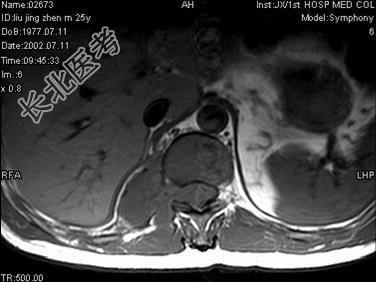

- 单项选择题男,25岁, 慢性腰痛伴间歇性跌倒半年,双下肢无力不能行走1月, MRI见下胸段椎管内肿瘤呈“哑铃”状应诊断为 ( )